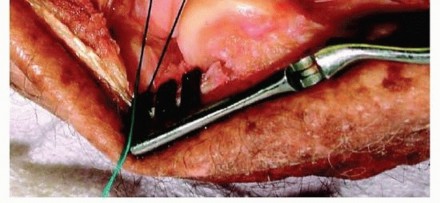

Step 3: Repair the LCL Complex. With the osseous stabilizers reconstructed, the lateral ligamentous tension must be restored. The avulsed LUCL and common extensor origin are repaired back to their anatomic footprint on the lateral epicondyle—the isometric point located at the center of capitellar curvature. This is typically achieved using robust suture anchors or transosseous bone tunnels. The repair must be tied with the forearm in pronation and the elbow at 90 degrees of flexion to ensure appropriate tensioning of the lateral structures.

Step 4: Assess Intraoperative Stability. Following LCL repair, the elbow is taken through a gentle range of motion. The surgeon must assess stability within a functional arc of 30 to 130 degrees of flexion-extension with the forearm in full pronation. If the joint remains concentrically reduced without subluxation or gapping on fluoroscopy, the procedure is concluded.